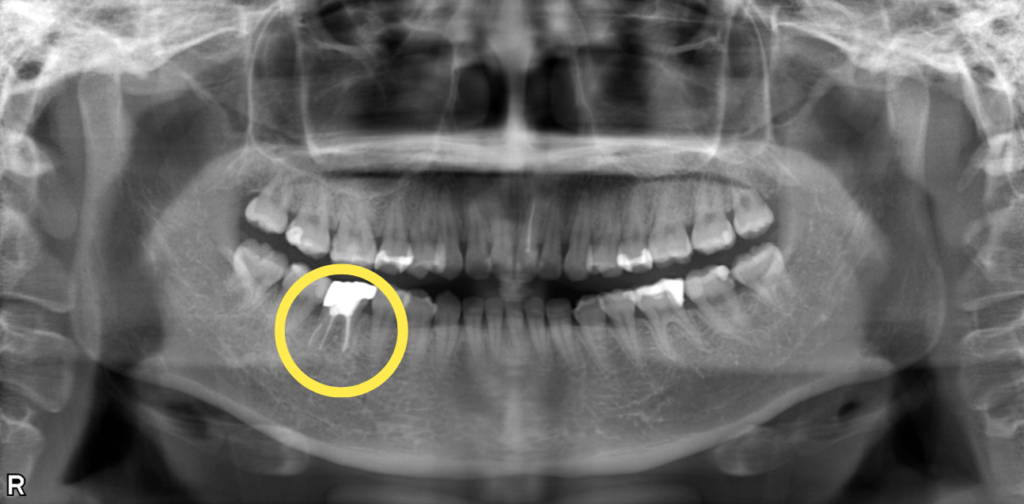

右下がかむと痛い・むし歯治療希望とのことで来院されました。 右下6番は根管内に感染を起こして根尖部に透過像を認めました。 根尖病変が非常に大きく、根管も複雑な形態をしていたため、まず歯科用CTを用いて3次元的な診断をしたのち、ルーペを使用して感染源の徹底的な除去および精密な根管治療を実施しました。 術後の経過は良好で、透過像も消失しています。根管治療後は、強度と審美性を兼ね備えたジルコニアクラウンで最終補綴を行いました。

| 概要 | 前歯に穴が開いているので治療して欲しい・右下がかむと痛いとのことで来院されました。 右下6番は根管内に感染を起こして根尖部に透過像を認めました。 根尖病変が非常に大きく、根管も複雑な形態をしていたため、まず歯科用CTを用いて3次元的な診断をしたのち、拡大ルーペを使用して感染源の徹底的な除去および精密な根管治療を実施しました。 術後の経過は良好で、透過像も消失しています。根管治療後は、強度と審美性を兼ね備えたジルコニアクラウンで最終補綴を行いました。 |